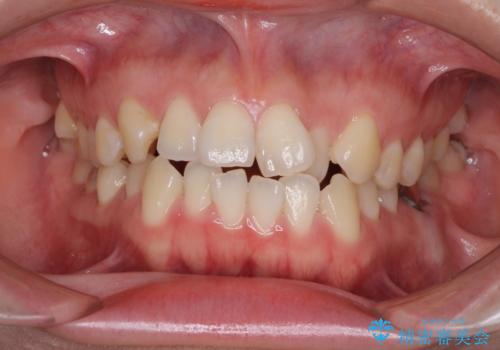

前歯のデコボコを治したい ワイヤー矯正

前歯のがたつき・すれちがい咬合を非抜歯で。流行の、格安マウスピースでは難しい、ワンランク上の治療